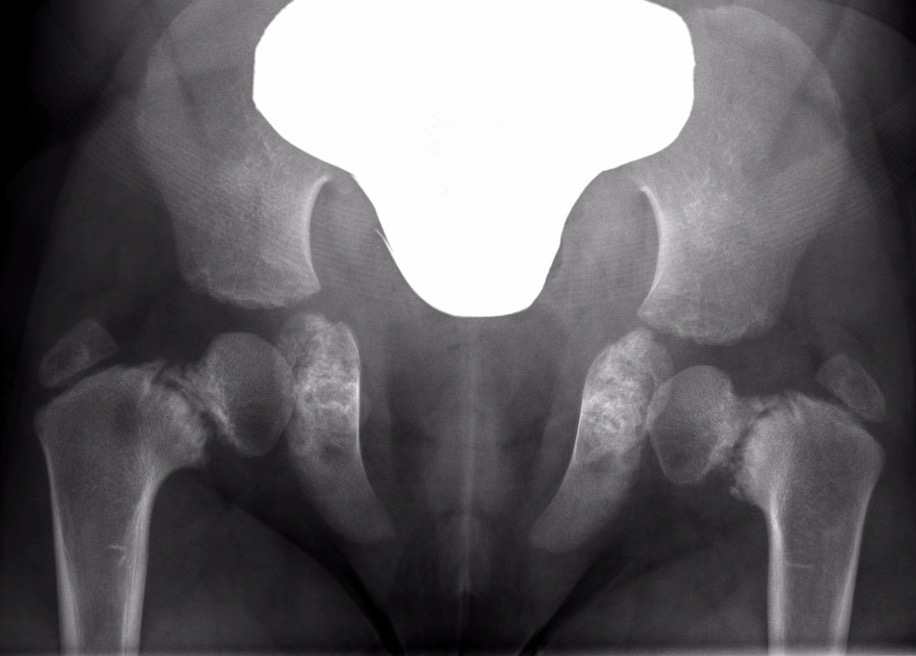

Xray

| Varus femoral neck | Inverted Y | Hilgenreiner's epiphyseal angle |

|---|---|---|

|

Neck-shaft angle < 125°

Normal is 150° in infant |

Inferior sclerotic metaphyseal triangle

Pathognomonic of developmental |

Angle between Hilgenreiner's & physeal line

Normal < 25°